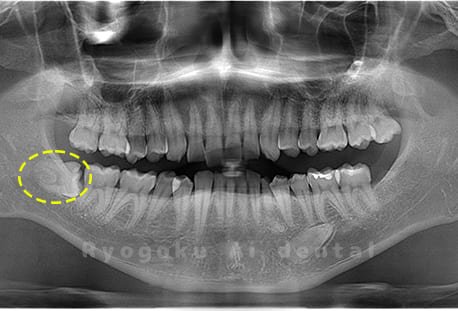

Case04

- 原因

- 上顎の親知らず、下顎の水平埋伏の親知らず

- 治療内容

- 上顎の親知らず、下顎の水平埋伏の親知らずを抜歯したケースです。

<リスク・副作用>

手術後は痛み、腫れ、痺れなどの副作用が生じる場合があります。